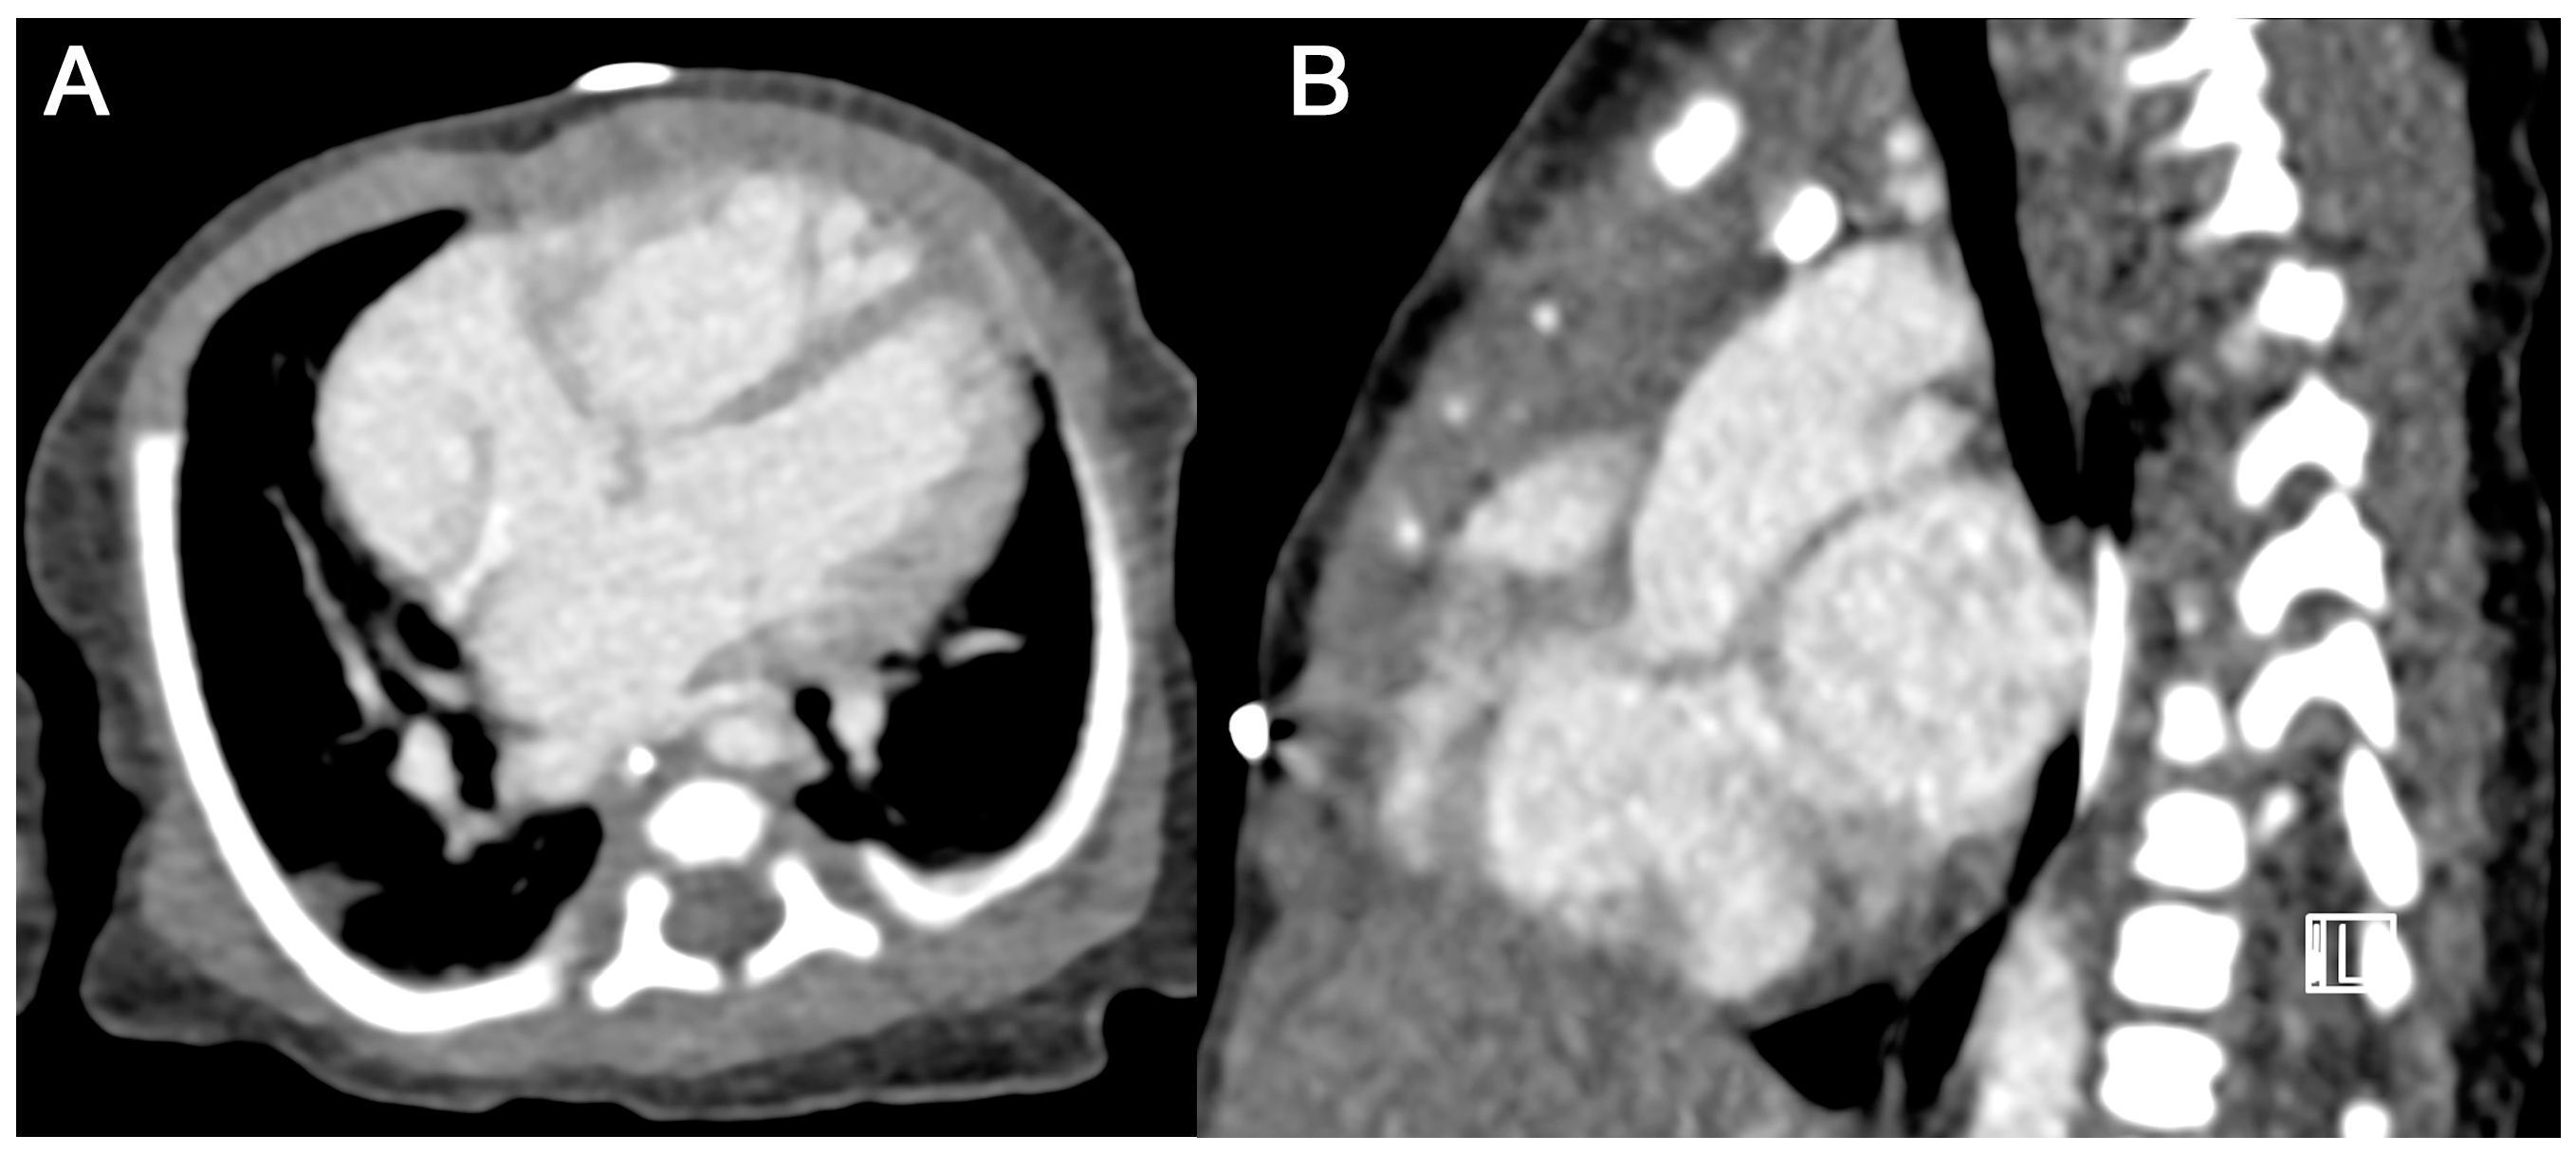

3.3.2. Subjective Image Quality